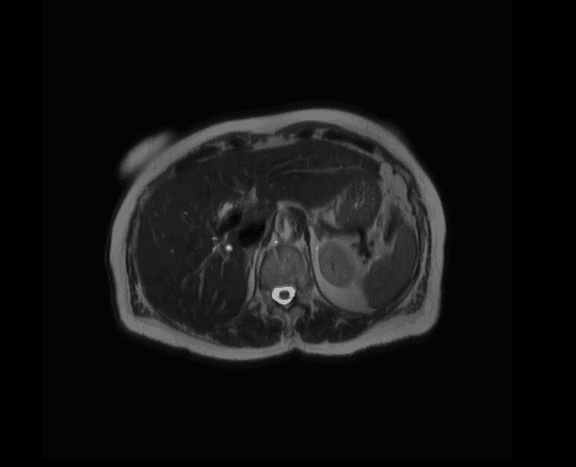

Eksempler på MR-scanninger

- Indre organer som lever, nyrer, binyrer, blære, milt og bugspytkirtel